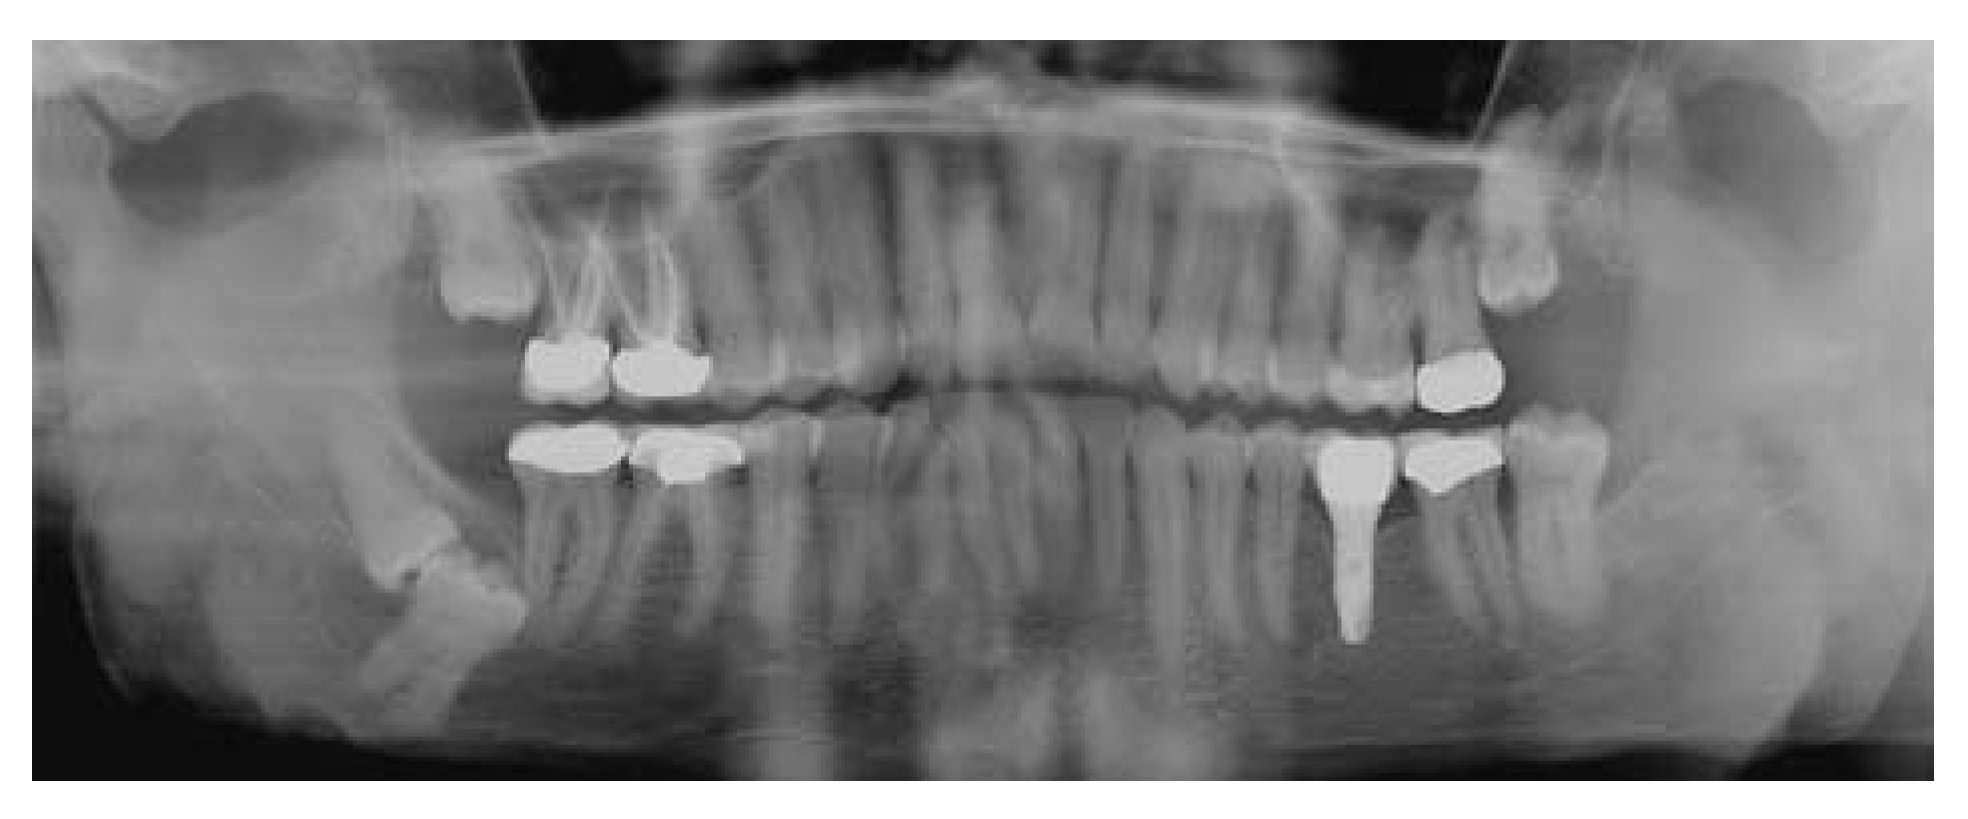

Report of a Case

![]() |